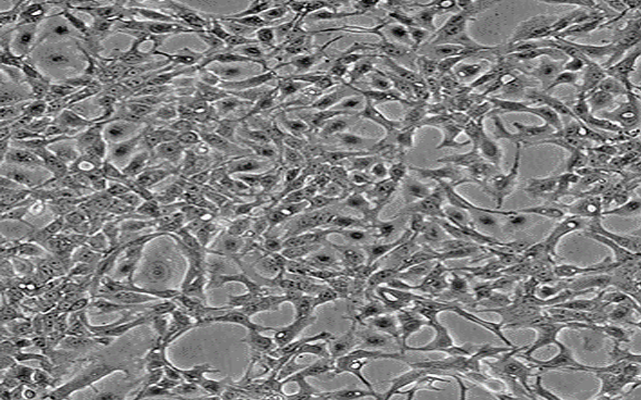

SJSA-1;人骨肉瘤细胞

D283 Med;人脑髓母细胞瘤细胞

MDA-MB-361;人乳腺癌细胞

H4;人神经胶质瘤细胞

SK-N-MC;人神经上皮瘤细胞

SK-N-AS;人脑神经母细胞瘤细胞

Daoy;人脑髓母细胞瘤细胞

DU4475;人乳腺上皮细胞

BT-20;人乳腺癌细胞

VIEW MORE